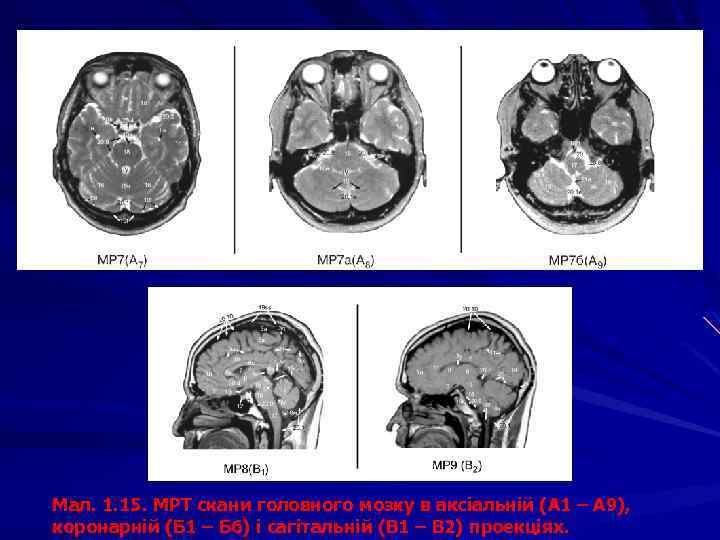

Мал. 1. 15. МРТ скани головного мозку в аксіальній (А 1 – А 9), коронарній (Б 1 – Б 6) і сагітальній (В 1 – В 2) проекціях.

Мал. 1. 15. МРТ скани головного мозку в аксіальній (А 1 – А 9), коронарній (Б 1 – Б 6) і сагітальній (В 1 – В 2) проекціях. 1 – частки великого мозку: 1 л – лобова, 1 т – тім’яна, 1 с – скронева, 1 п – потилична, 1 о – острівцева, 1 нц – напівовальний центр. 2 - щілини великого мозку: 2 а – поздовжня, 2 б – поперечна. 3 т – потилично-скронева, 3 у – каудально -таламічна, 3 ф - 3 – борозни: 3 а – центральна, 3 б – бічна, 3 в – передцентральна, 3 г – верхня лобова, 3 д – нижня лобова, 3 е – зацентральна, 3є – нюхова, 3 ж –потиличні, 3 и – шпорна, 3 з – півмісяцева, 3і – верхня скронева, 3ї – нижня скронева, 3 к – острівцеві, 3 л – мозолистого тіла, 3 м – поясна, 3 н – підтім’яна, 3 н – нижня тім’яна, 3 о – тім’яно-потилична, 3 п – каудально-таламічна, 3 р – гіпокамп 3* звивини: 3 а* – передцентральна, 3 б* – зацентральна, 3 в* – верхня лобова; 3 г* – середня лобова, 3 д* – нижня лобова, 3 ж*– верхня скронева, 3і* – середня скронева; 3 и* – нижня скронева; 3 к* – верхня тім’яна часточка, 3 л* – нижня тім’яна часточка; 4 – шлуночки мозку: I, ІІ – бічні шлуночки: п – передній, з – задній, н – нижній роги, с – судинне сплетіння, т – тіло; III шлуночок: з – зорова, л – лійкова заглибини; с – міжталамічна спайка, о – міжшлуночкові отвори; IV шлуночок: б – бічний, с – серединний отвори. 5 – водопровід мозку. 6 – мозолисте тіло: 6 в – валок, 6 с – стовбур, 6 к – коліно, 6 д – дзьоб, 6 п – променистість; 6* – передня комісура (спайка). 7 – прозора перегородка: 7 п – порожнина прозорої перегородки. 8 – хвостате ядро. 9 – таламус, 9* – гіпоталамус. 10 – смугасте тіло. 11 – внутрішня капсула: 11 п – передня ніжка, 11 з – задня ніжка, 11 к – коліно. 12 – гіпофіз. 13 – зорове перехрестя. 14 – шишкоподібне тіло. 15 – ніжка мозку, 15 а – червоне ядро, 15 б – горбки чотиригорбистості. 16 – мозочок: 16 ч – черв ’як, 16 м – мигдалик, 16 я – ядра. 17 – довгастий мозок, 17 ц – центральний канал. 18 – міст. 19 – кровоносні судини, 19 А – мозкові артерії: 19 а – передня, 19 m – середня, 19 p – задня; 19 v – вертебральна, 19 k – сонна, 19 c – мозочкова; 19 V – мозкові вени: 19 iv – внутрішня вена мозку; 19 vj – велика вена (Галена); 19 S – синуси: 19 r – прямий, 19 ks – стік синусів, 19 ss – сагітальний синус. 20 – цистерн підпавутинного простору: 20. 1 – мозочково-довгаста (бульбарна); 20. 1 а – валекула; 20. 1 м – верхня мозочкова; 20. 2 – бічної ямки великого мозку; 20. 3 – міжніжкова; 20. 4 – зорового перехрестя; 20. 5 – навколомозолиста; 20. 6 – великої вени (чотиригорбистості); 20. 7 – оточуюча; 20. 8 – мосто-мозочкова; 20. 9 – цистерни моста; 20. 10 – конвекситальний субарахноїдальний простір. Присінковозавитковий нерв – позначено*, мозочковий серп – стрілкою, мозочковий намет – подвійною стрілкою. 21 – кістки черепа: 21 р – решітчаста, 21 л – лобова, 21 к – клиноподібна, 21 тс – турецьке сідло, 21 т – тім’яна, 21 п – потилична, 21 с – скронева, 21 сх – схил. 22 – ламбдоподібний шов. 23 – великий потиличний отвір. 24 - орбіта.